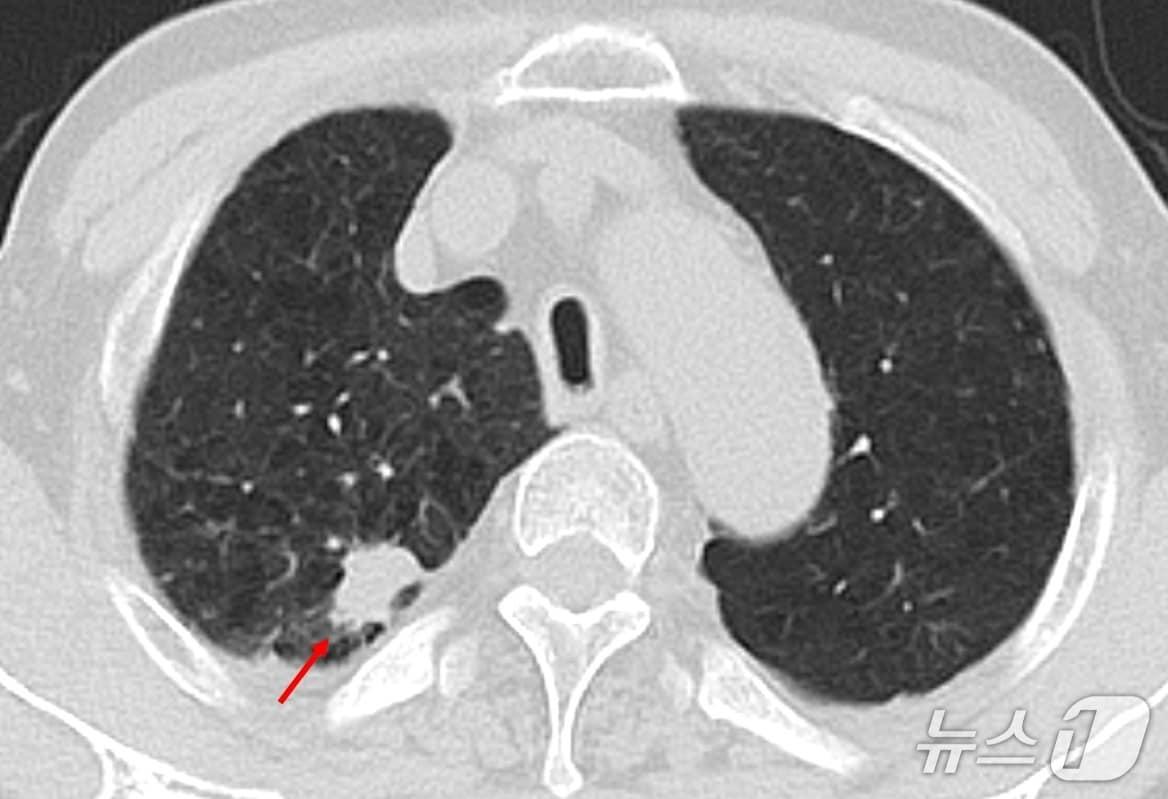

본문 이미지 - 저선량 흉부 CT 검사에서 폐결절 확인 사진(한림대학교동탄성심병원 제공)

저선량 흉부 CT 검사에서 폐결절 확인 사진(한림대학교동탄성심병원 제공)